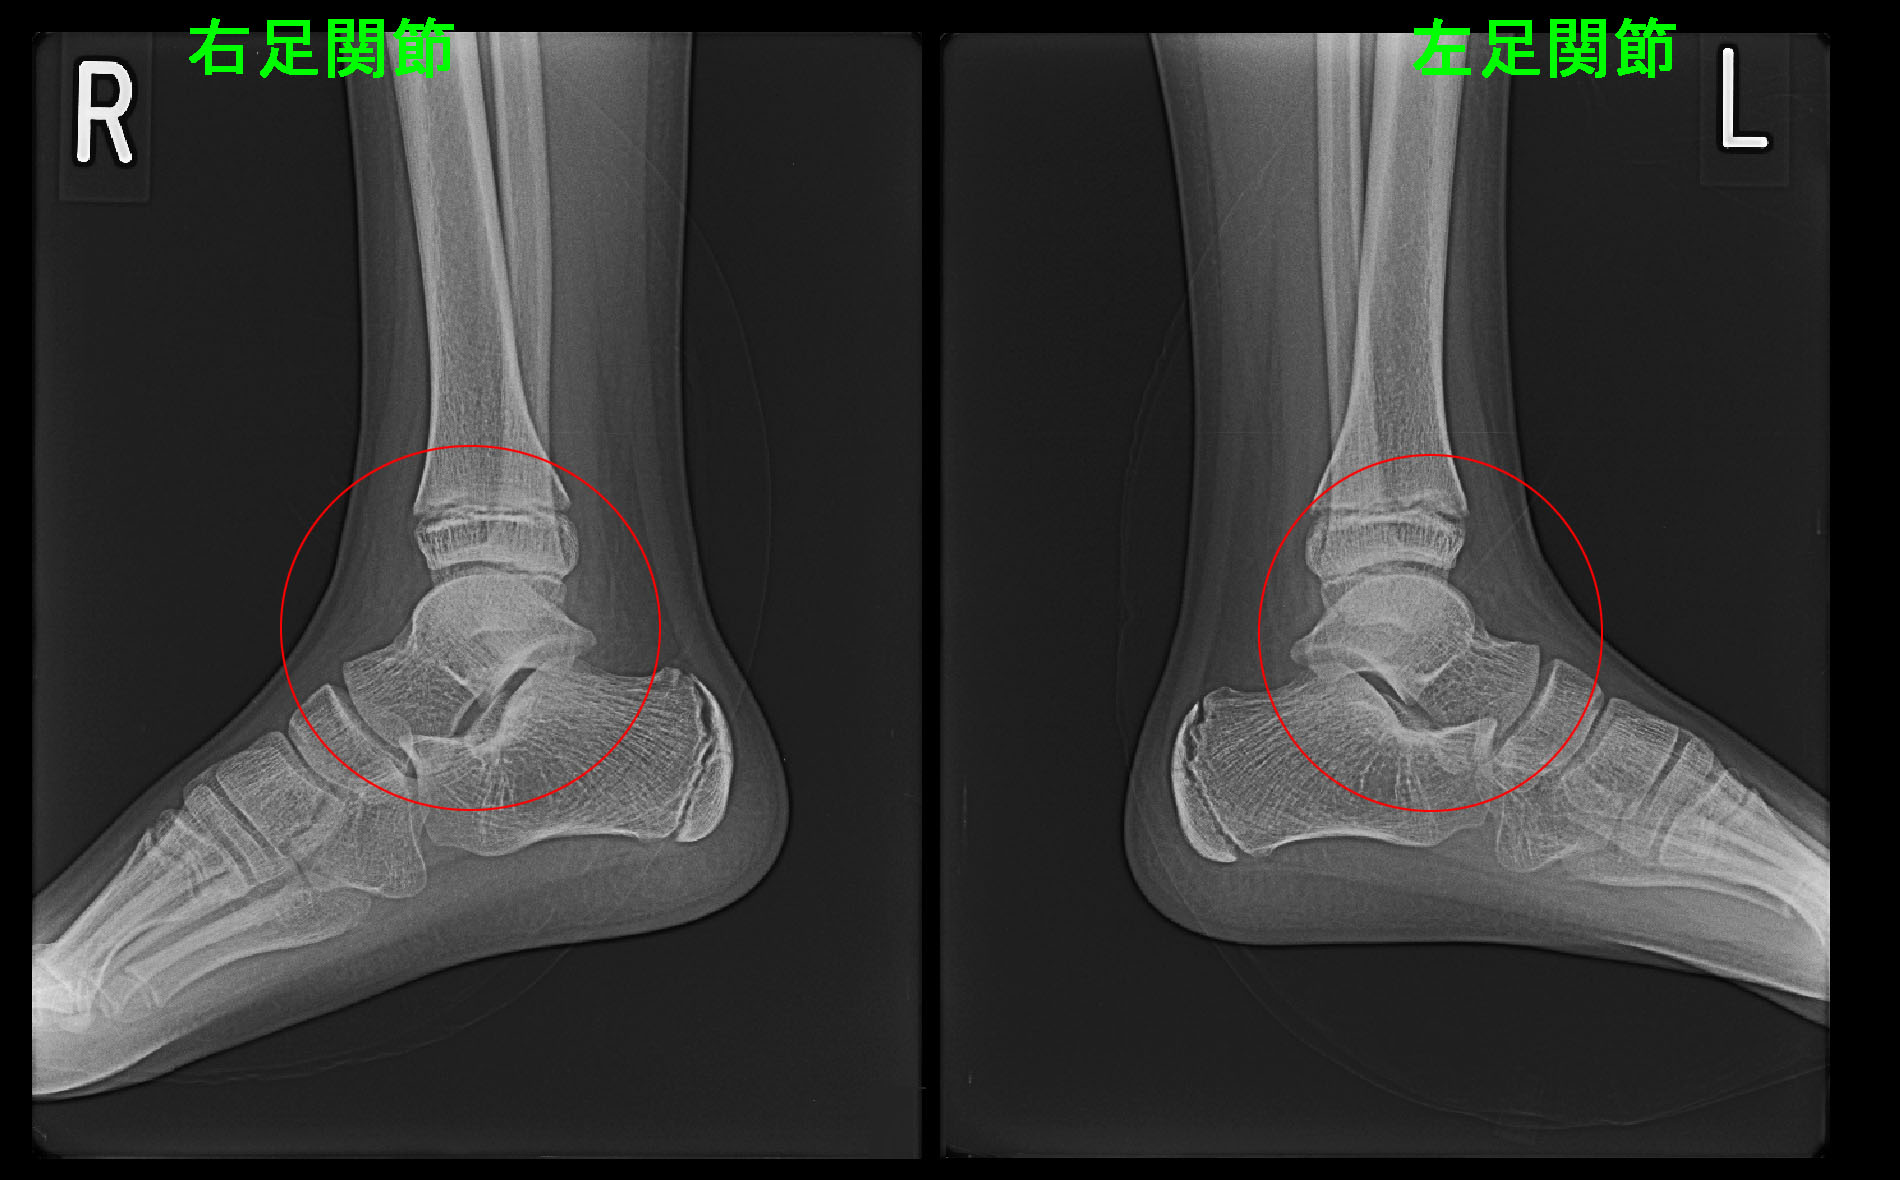

17才の高校2年生女子バレーボール部の選手です。平成24年4月28日に左足部外側痛で受診されました。投薬と局所注射で対応したのですが、痛みはかえって増悪し、5月8日に跛行を呈し(びっこの状態です)、再診されました。そこでMRI検査を行っています。

左足では立方骨という骨が高輝度所見を呈し、疲労骨折の診断となりました。

この患者さんは服薬の対応で、同時期のインターハイ大会をチームのエースアタッカーとして気合いと根性で乗り切りました。その大会を最後に引退したのですが、5か月経過した10月20日に受診されました。体育などでも痛くないので、どの程度良くなったかMRI検査で確認したいという意向でした。その時のMRI画像を提示します。

MR2.jpg

左立方骨の高輝度領域はかなり縮小していますが、全く正常化しているわけではありませんでした。